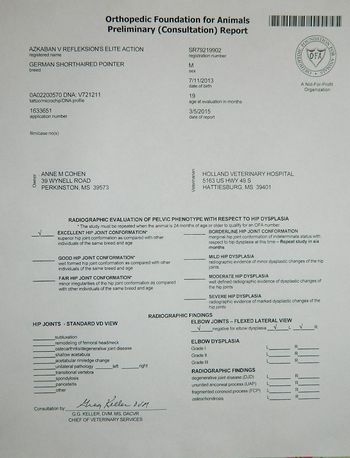

Health Clearances

GSP-16906E25M-VPI

GSP-EL2371M25-VPI

GSP-CA1960/19M/P-VPI

GSP-CA1960/25M/C-VPI

GSP-EYE328/25M-VPI 14,15

GSP-CD688/6M-NOPI

GSP-LD93/13M-PI

GSP-VW46/12M-NOPI

GSP-DL14/16M-VPI

GSP-DM14/25M-VPI